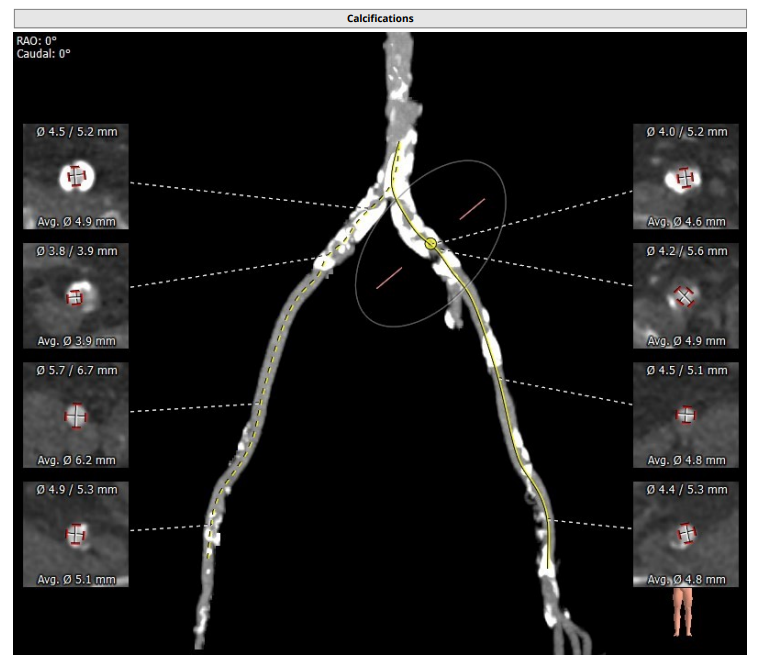

术前CT评估报告:

瓣环平均直径:26.3 mm,左室流出道平均直径:27.3 mm

主动脉窦部: 28.7 mm, STJ : 30.5 mm

左冠高度7.1mm, 右冠高度13.2mm.

升主动脉未见明显扩张,右侧股动脉符合入路条件

患者为TYPE1型二叶瓣,重度钙化,左右可见钙化脊,左冠高度低,可能存在较高的冠脉风险,该患者对于瓣膜释放位置要求较高,容错空间很小,法式窦结构可,需要在术中球囊扩张时着重观察冠脉即刻情况且做出相应判断。左室大小可,升主动脉未见明显扩张,心脏角度43°。